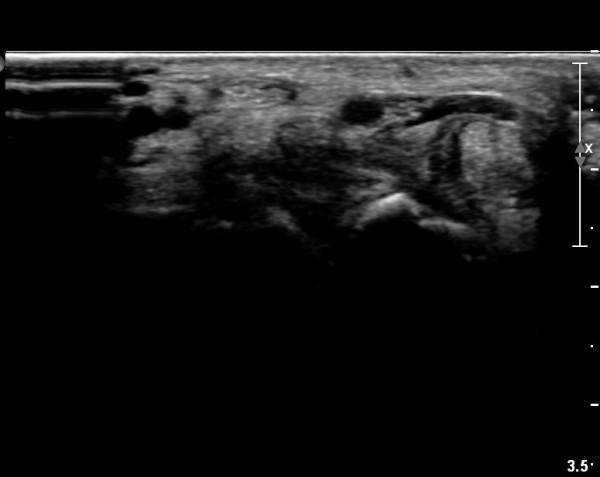

ÃÊÀ½ÆÄ ¼Ò°ß :  ¼Õ¸ñ±ÙÀ§ºÎ Ⱦ´Ü¸é°Ë»ç¿¡¼­ ¼Õ¸ñ±¼±Ù°Ç(FCR)°ú Ç¥Ãþ ¼Õ°¡¶ô ±ÁÈû±Ù(FDS) »çÀÌ¿¡

Á¤Á߽ŰæÀÌ Á¤»óÀûÀÎ ¾ç»óÀ¸·Î º¸ÀÓ(»çÁø 1).

Å½ÃËÀÚ¸¦ ¸»´ÜÀ¸·Î À̵¿ÇÏÀÚ  Á¤Áß½Å굥 ¿äÃø ÀϺΰ¡ Àú¿¡ÄÚ Á¾±«·Î °üÂûµÊ(»çÁø 2).

ÀÌ·± ¸ð½ÀÀº ¼Õ¸ñÀÇ ¿ù»ó°ñ ºÎÀ§(»çÁø 3, 4)¸¦ Áö³ª ¼ö±Ù°ü ±ÙÀ§ºÎ ±îÁö À̾îÁü(»çÁø 5).